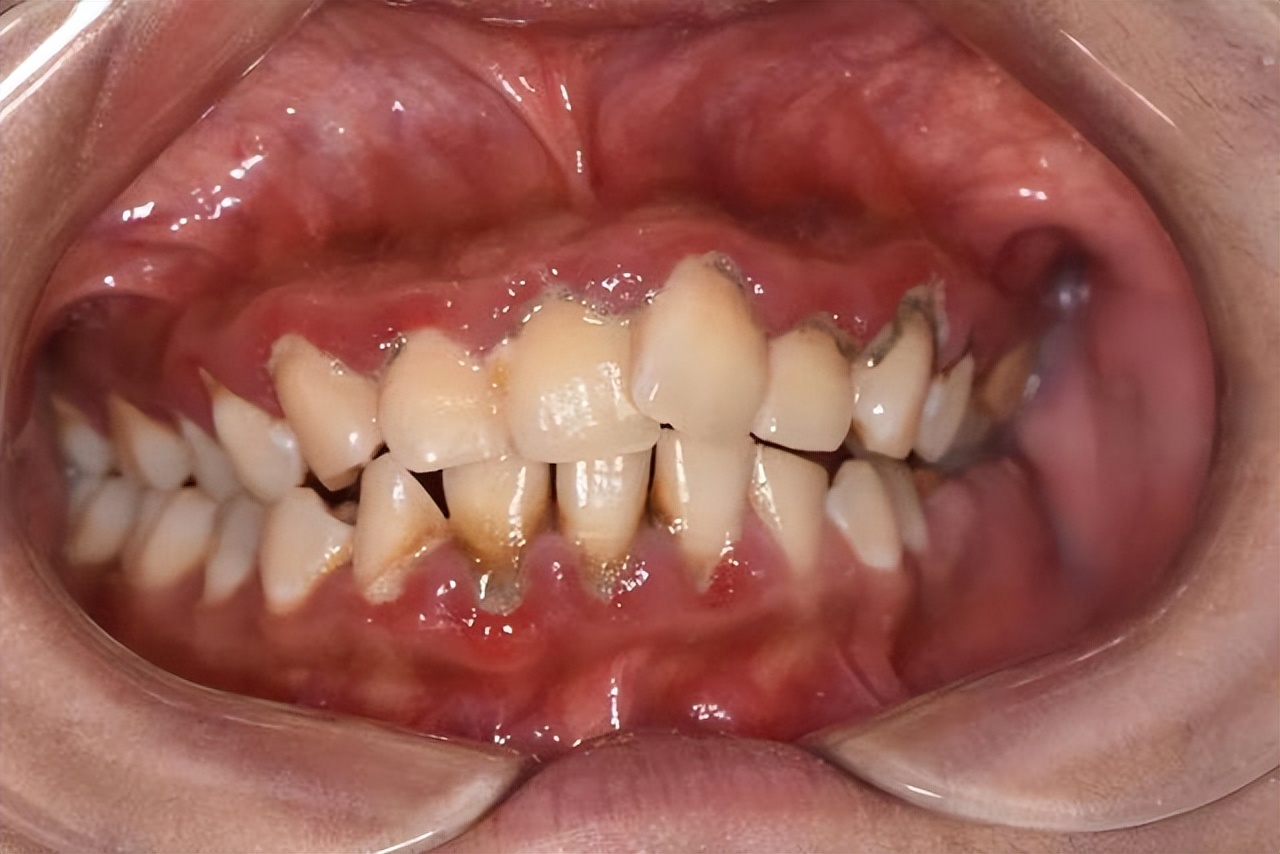

2、牙周炎

这种情况多是由于牙菌斑侵犯牙周组织造成的,部分患有全身性疾病的人群也容易出现这种情况。牙周炎初期表现为:口臭、牙龈出血、红肿、疼痛等症状;如果不及时治疗,后期会发展成:牙龈萎缩、牙槽骨吸收,牙齿松动等症状。

建议:及时进行 龈上/龈下洁治,做好口腔清洁工作。